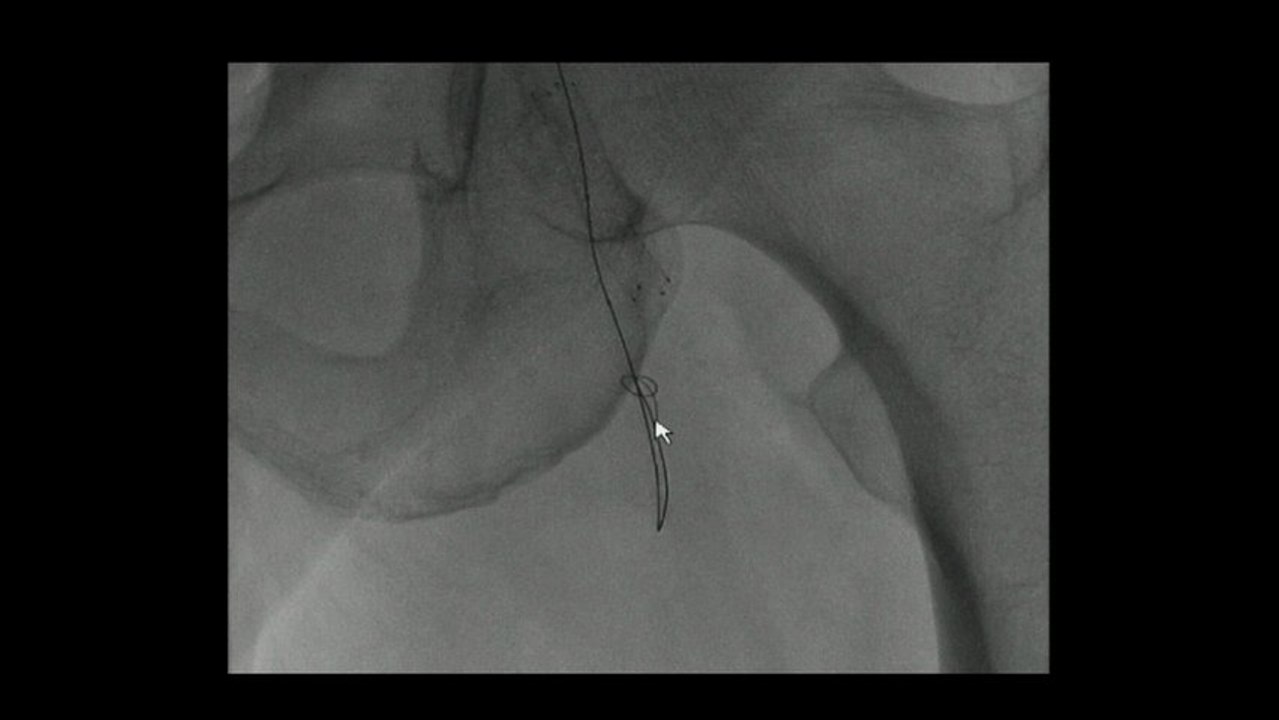

Angioplasty of BTK reocclusion by double accesses

Retrograde SFA recanalization by popliteal artery approach